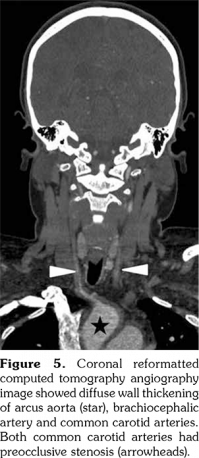

A 14-year-old female patient referred to our clinic with headache and dizziness for two weeks and loss of consciousness for about 10 minutes. On admission, the blood pressure was 90/60 mmHg and all peripheral pulses were palpable. Her body weight was above 97th percentile for her age and body mass index was 33. The fundus examination and other organ systems were essentially normal. Laboratory studies revealed erythrocyte sedimentation rate (ESR) as 108 mm/hour and C-reactive protein (CRP) as 7.5 mg/dL (0-0.8), while other measurements were normal. Urinalysis revealed microscopic hematuria and proteinuria of 31.9 mg/m2/hour in 24-hour urine collection. The cerebrospinal fluid examination showed no abnormalities. Cranial magnetic resonance imaging (MRI) showed multiple millimetric hyperintense deep white matter lesions on T2-weighted imaging (Figure 1). Intracranial and extracranial arteries were normal in magnetic resonance angiography (MRA). Renal biopsy findings were interpreted as FSGS (Figure 2). Patient was considered as cerebral vasculitis and incidental FSGS. Pulse methylprednisolone therapy for three consecutive days was initiated and continued with oral prednisolone. At four years of follow-up, proteinuria decreased to 5-15 mg/m2/hour, and ESR and CRP were normal. Repeated brain MRI and MRA examinations showed no new lesions. Four years later, at the age of 18, on a routine examination, both radial artery pulses were absent and the blood pressure could not be measured. Significant bruit was heard on the left carotid artery. Laboratory studies revealed ESR as 43 mm/hour and CRP as 2.46 mg/dL. Aortic MRA revealed diffuse wall thickening and contrast enhancement in the arcus aorta and its many main branches (Figure 3). Takayasu arteritis diagnosis was established according to the European League Against Rheumatism/ Paediatric Rheumatology International Trials Organisation/Paediatric Rheumatology European Society criteria.[2] Methotrexate was begun, and daily prednisolone was continued. Four months after the diagnosis of TA, left-sided hemiparesis developed. Brain MRI demonstrated a wide cerebral infarct at the right anterior vascular territory (Figure 4). Brain and neck computed tomography angiography showed total occlusion of the right internal carotid artery. Vascular involvement of the right common carotid artery was progressed to preocclusive stenosis. Diameters of the right anterior and middle cerebral arteries were thin and fed by the posterior and anterior communicating arteries (Figure 5). Tocilizumab treatment was started at 8 mg/kg every four weeks. At follow- up with 2.5 years of tocilizumab treatment, the patient's clinical condition improved slightly, and no new symptoms developed. A written informed consent was obtained from the patient.

Renovascular hypertension is the most common renal manifestation of TA; however, proteinuria and nephrotic syndrome are both very rare and usually caused by factors other than FSGS. Four years before the diagnosis of TA, our patient was diagnosed as cerebral vasculitis. In the same period, renal biopsy performed due to proteinuria was reported as FSGS. Cerebral vasculitis and TA in our patient may be coincidental with FSGS but it was supposed that immune complex deposition and vascular lesions caused glomerular ischemia in TA.[7] Kuroda et al.[8] reported a 50-year-old female patient with TA who developed proteinuria and renal dysfunction with glomerulopathy mimicking membranoproliferative glomerulonephritis. They argue that increased vascular endothelial growth factor and interleukin (IL)-6 levels may cause renal disease.

Microvascular involvement might lead to glomerular ischemia and obesity might be an additional factor for developing FSGS in our patient. FSGS is a pattern of histologic injury rather than a disease. In obese patients, elevated plasma levels of leptin through upregulation of transforming growth factor beta 1 may also predispose to glomerulosclerosis.[9]